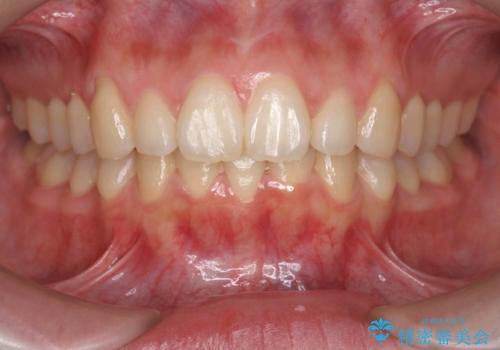

![[ インビザライン矯正 ] マウスピース矯正で治す、前歯のガタつきの症例 治療前](https://seimitsushinbi.jp/wp/wp-content/uploads/2022/02/324533f54aaa29eca08b0a9fdd3af7e2-500x350.jpg?v=1644473292)

![[ インビザライン矯正 ] マウスピース矯正で治す、前歯のガタつきの症例 治療後](https://seimitsushinbi.jp/wp/wp-content/uploads/2022/02/IMG_1698-500x350.jpg?v=1644473356)